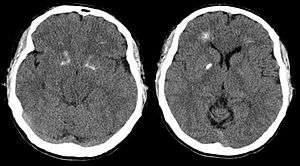

Brain computer tomography cuts of the person, demonstrating basal ganglia and periventricular calcification.[6] | |